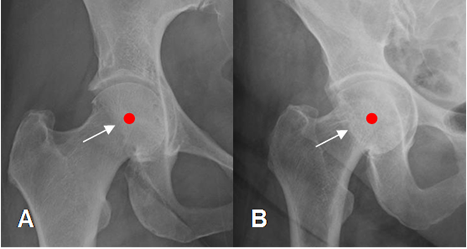

Fig 99. Pinzamiento tipo pincer. Signo de la pared posterior.

A y B: Rx. El reborde posterior es lateral, al centro de la cabeza femoral.